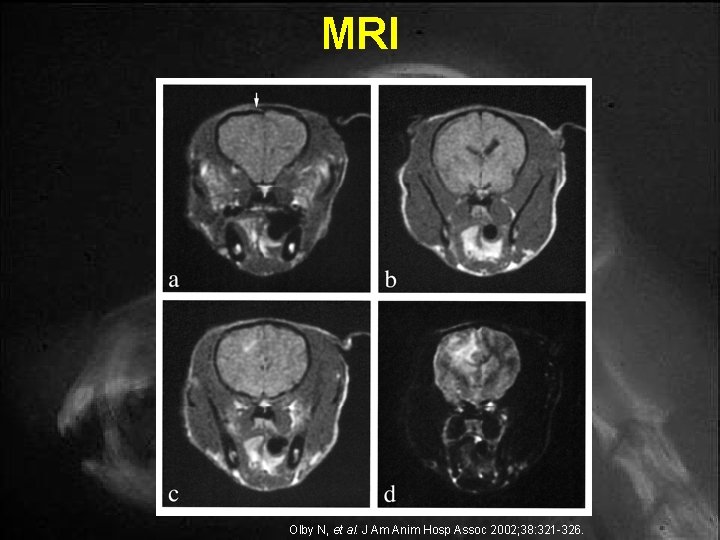

MRI Olby N, et al. J Am Anim Hosp Assoc 2002; 38: 321 -326.